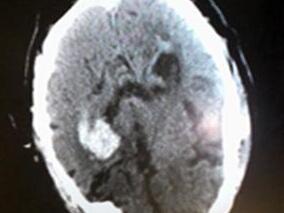

1小时条评论【病例摘要】 老年男性患者因肺栓塞使用华法林、低分子肝素钙治疗,华法林剂量从3mg逐渐增至5.25mg,低分子肝素钙首剂量4100IU后使用6150IU,q12h皮下注射。19天后患者出现喷射性呕吐,头颅CT示脑出血,破入脑室,出血量约30ml,凝血检查示国际标准化比值为1.92。...